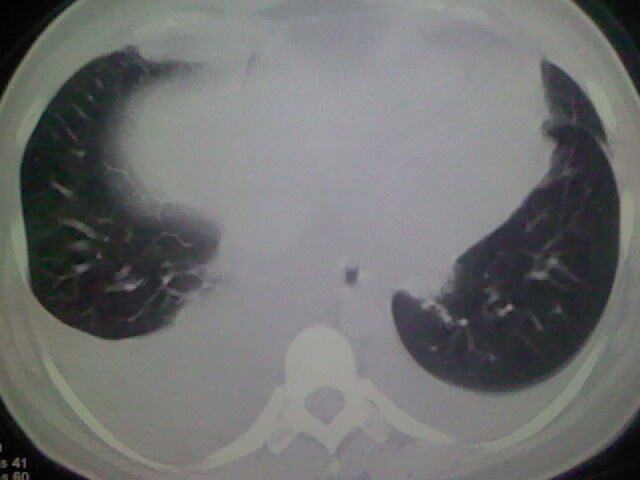

女,24,剖腹产后,突觉胸痛,干咳,不能平卧

双肺“肺泡性肺水肿” “胸腔积液”!

考虑肺梗塞、肺水肿,双侧胸腔积液

全心衰导致积液、肺水肿。不知手术前有无心脏病变?

产后心衰